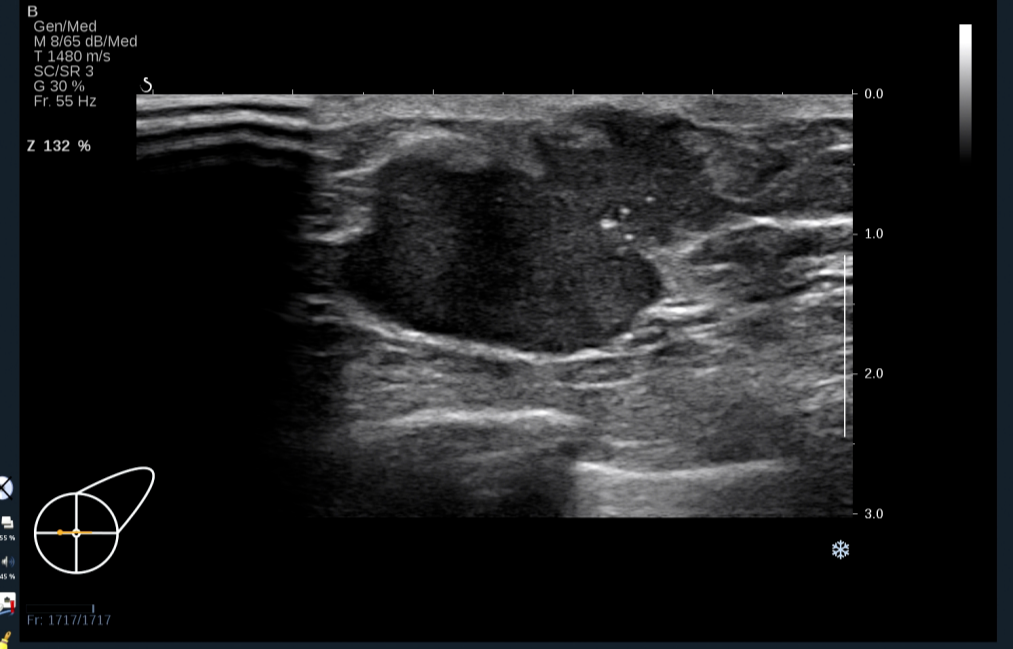

超声可见:左侧乳腺乳头后方可见少量腺体组织回声,其内可见一低回声团,大小约31.6×18.8×17.6mm,形态不规则,周边呈毛刺样,边界欠清,内回声不均匀,可见数个点状强回声。

图1 探头横切扫查示:左乳乳头后方不规则低回声团伴多发钙化

图片来源:作者提供